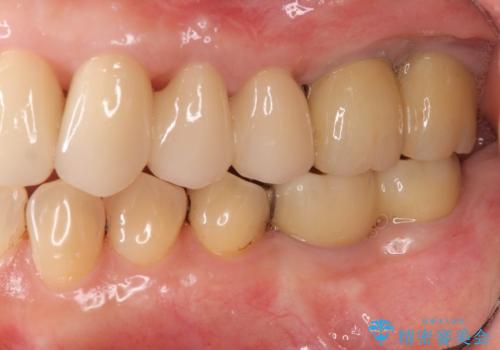

強い咬合力に対抗する歯周補綴

- 夜間のくいしばり、はぎしりが激しく全体的な歯周病が進行し、治療を希望され来院されました。

歯周ポケットの徹底的な除去を行なったのち、歯の揺れを抑え、過大な力がかからぬよう連結クラウン(歯周補綴)を行い強大な力に対抗します。